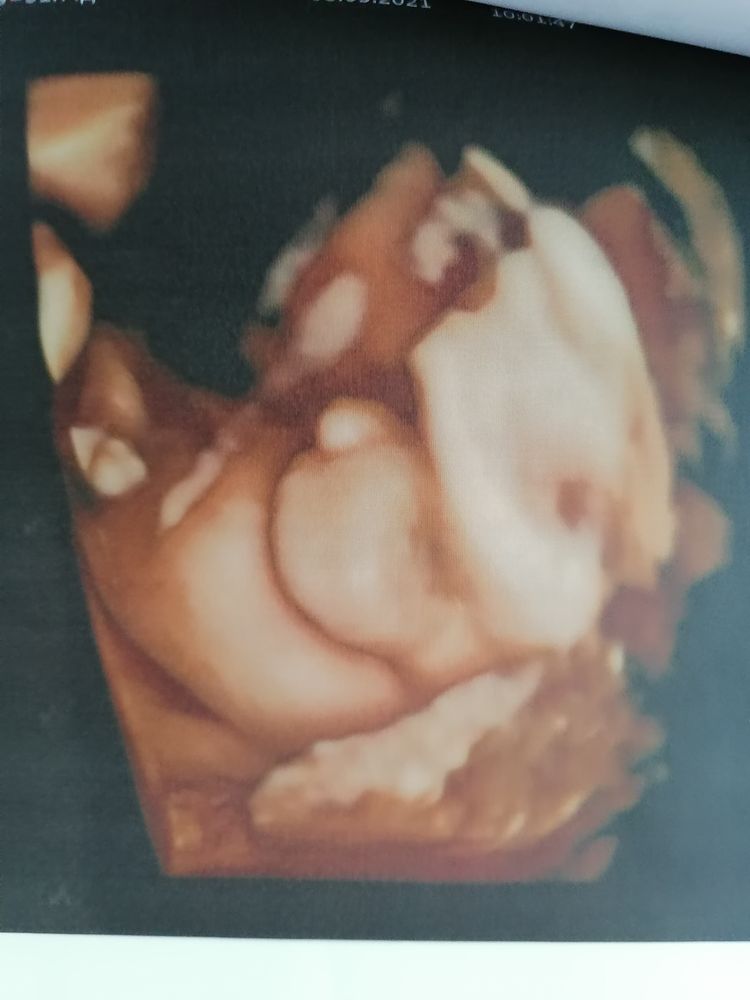

Ну а теперь о сегодняшнем скрининговом узи в 31.4 недели у Пятых Н. С.

Всё как обычно отлично, ощущение, что она нас помнит, все расспросила перед узи, пообщались. Вообщем мы с мужем довольны на все 200%. Очень тщательно рассмотрела каждый орган сыночка. Долго пытались его развернуть что бы увидеть личико и у нас получилось. Включала 4Д узи ждали пока он улыбнётся и опять таки дождались🥰.

По узи с сыночком все тттттт отлично, растёт чётко в срок, уже нет опережение. Все органы на месте, все с ними хорошо. Врач сказала, что очень большие кулачки и ножки🙈. Да я и сама видела, прям такая мужицкая рука и чувствую ух как эти кулачки и ножки🥰.

Весит 1890, что норма для 31.5 недели.

Ну и фоточки сыночка 👶🙏🙏🙏🥰. Люблю его сил нет❤️❤️❤️

Улыбашка мой

Бубенчики уже опустились в машонку👶.